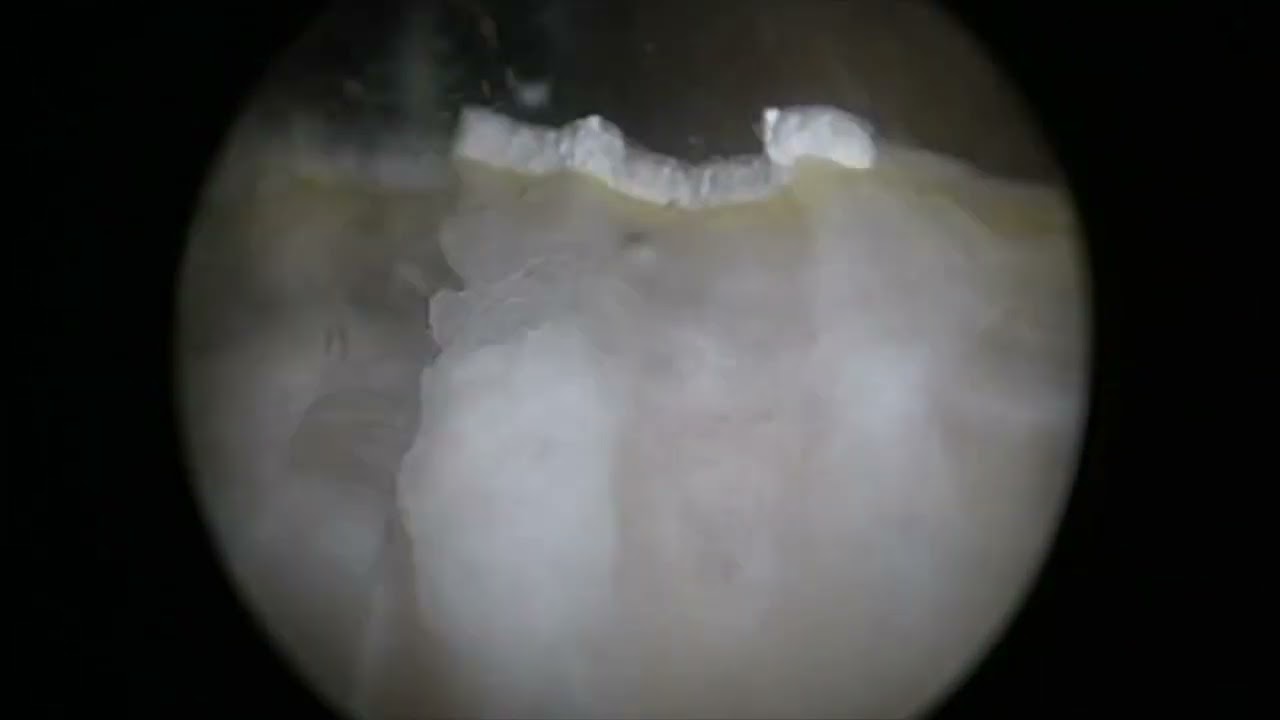

A lo largo de los años, me he especializado en tratamientos como la enucleación prostática con láser Holmio (HoLEP), técnica en la que fui pionero y que hoy en día continúa ofreciendo excelentes resultados para quienes viven con hiperplasia prostática.

Enucleación prostática con láser

Cirugía láser para cálculos en vía urinaria